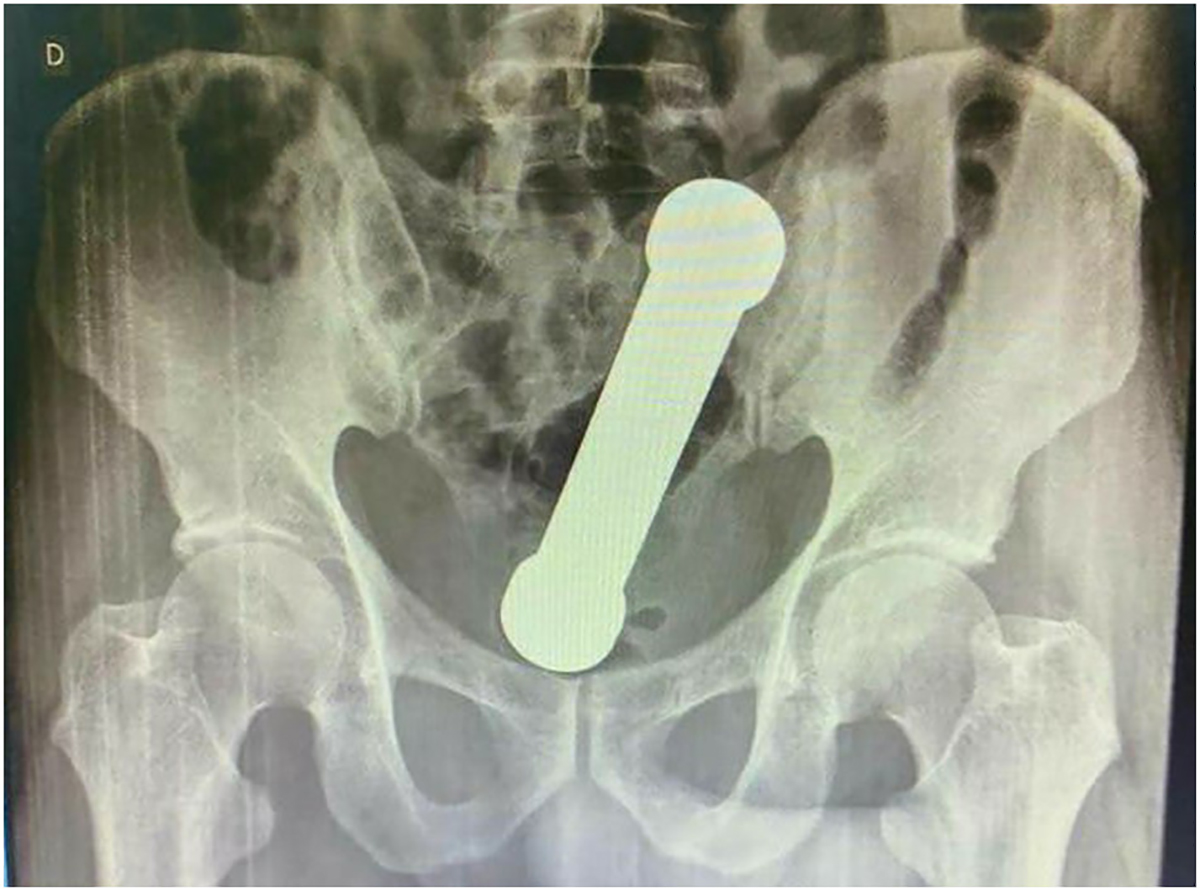

ŽALIO SE NA BOLOVE Lekari zanemeli kad su videli rendgenski snimak: Iz rektuma mu izvađen teg od 2 kilograma!

Šokantan slučaj je zabeležen u Brazilu.